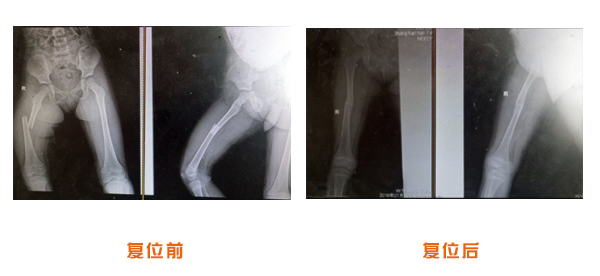

尺橈骨骨折治療前后